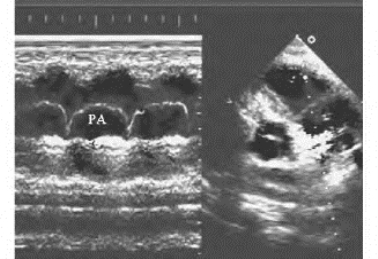

1.14.3第三节 M型超声心动图检查、测量方法及正常值

1.14.3.1一、检查方法、分区和命名

1.14.3.2二、M型波形的主要用途